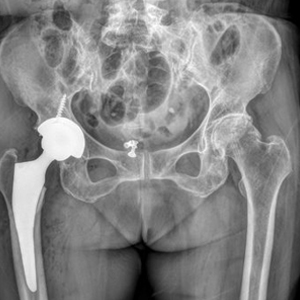

고관절은 몸의 중심에서 가장 가까운 관절이기 때문에 무혈성 괴사, 퇴행성 관절염, 골절 등으로 고관절에 통증이 발생하면 기본적인 일상적인 생활조차 어렵게 됩니다. 따라서 이렇게 손상된 고관절에는 인체에 무해한 ‘티타늄 금속 합금과 4세대 세라믹’으로 이루어진 고관절 인공관절 수술을 시행하게 됩니다.

고관절 인공관절 수술은 수술 후 효과적인 통증 조절로 조기 보행을 가능하게 하여 장기간 누워있어서 생기는 합병증을 줄이고, 정확한 수술을 통해 수술 후 탈구되지 않도록 하는 것이 가장 중요하므로 수준 높은 의료진의 실력이 결과의 성패를 좌우합니다.

고관절 인공관절 수술 후